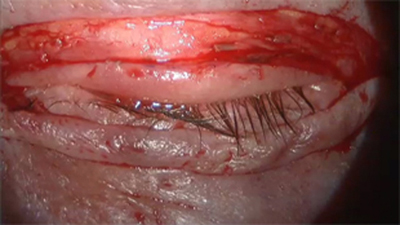

El día 1- I- 07 se le practica la reintervención con cirugía de Mohs y al día siguiente la reconstrucción palpebral con un injerto libre de cartílago de concha auricular y un colgajo bipediculado, músculo cutáneo de Tripier. (Figura 14)

Procedimos a la toma de un colgajo músculo cutáneo, bipediculado de Tripier en la forma y detalle ya descrita anteriormente, para transponerlo sobre el injerto de cartílago, y suturar la piel con Nylon 6-00 en una forma continua.

Figura 16 Post-op inmediato de injerto cartilago y colgajo de tripier